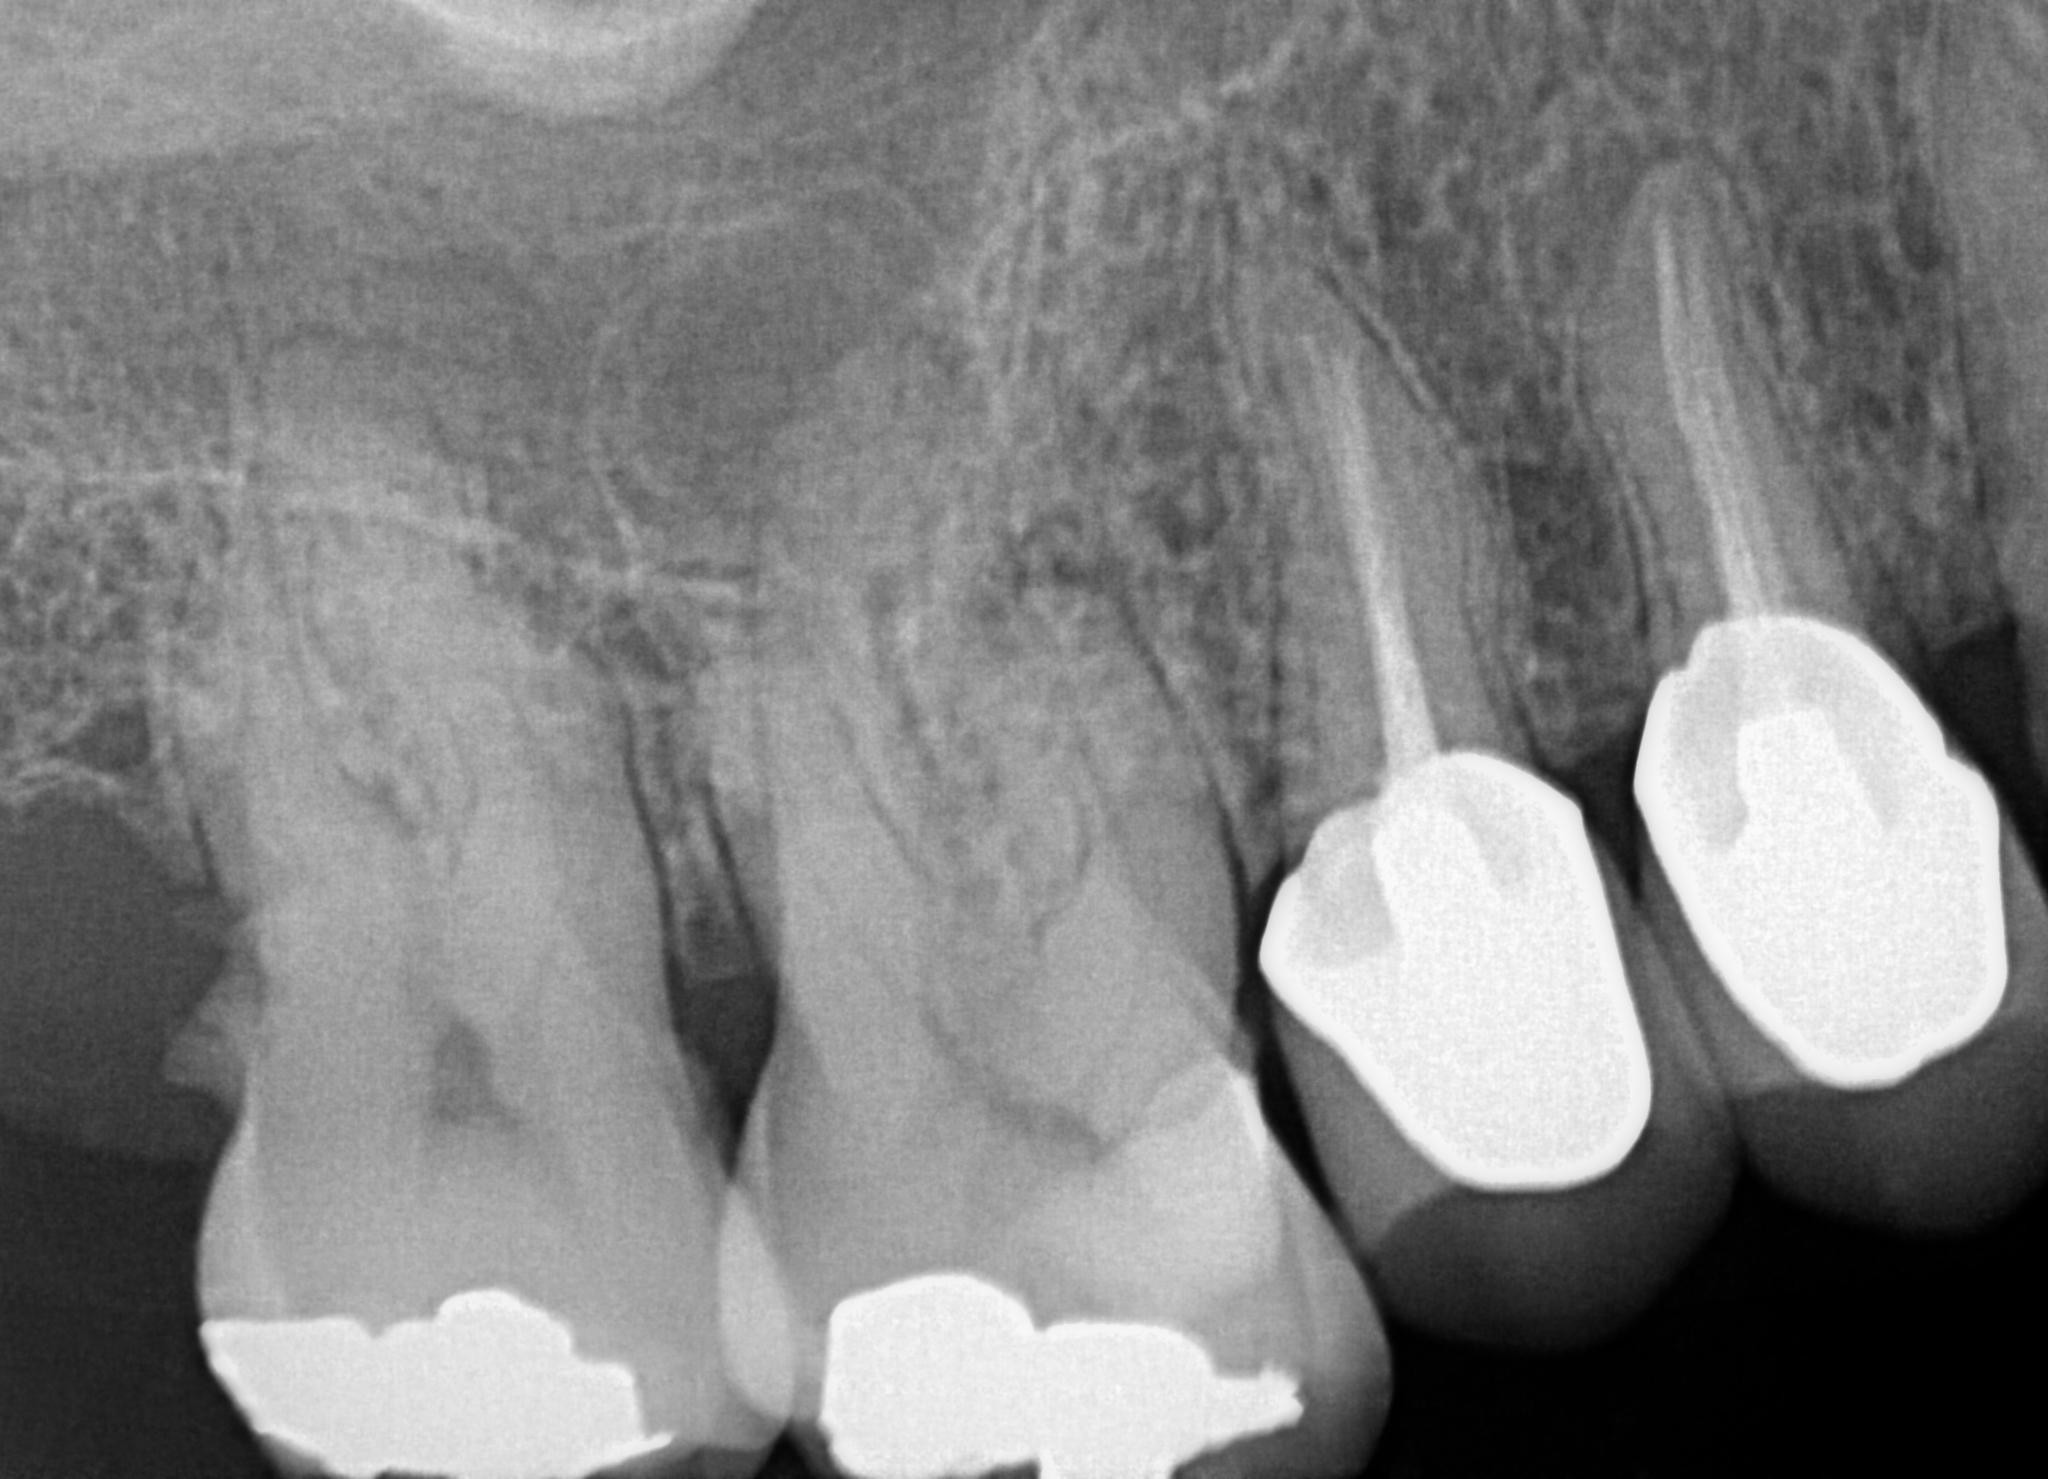

31. What option can be selected for the crown over the teeth # 2.4 and 2.5?